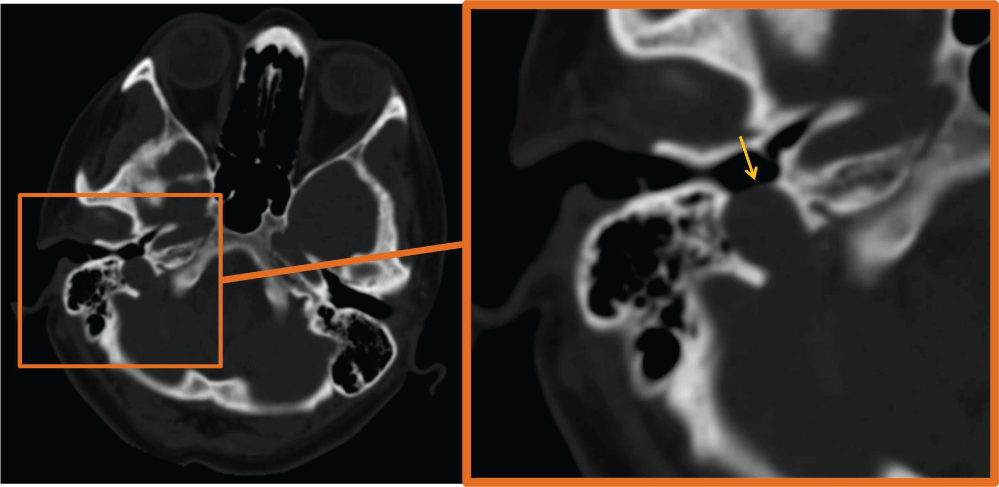

A 41-year-old female patient with 2-year history of tinnitus in right ear admitted to our clinic. The patient underwent temporal bone CT imaging. CT demonstrated right dehiscent high riding jugular bulb with absence of the right sigmoid plate (Figure 1).

Figure 1: CT demonstrates right dehiscent high riding jugular bulb with absence of the right sigmoid plate (arrow).